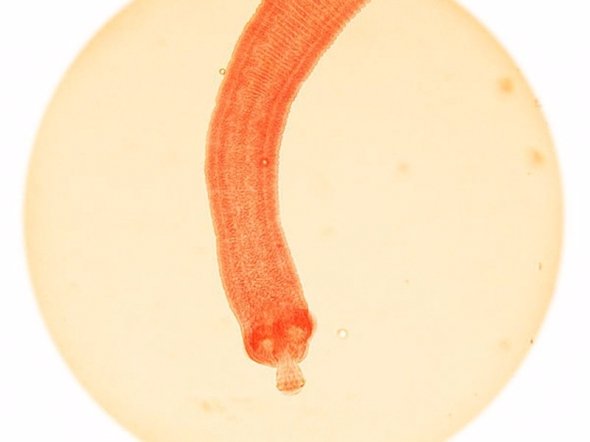

Стрічкові черв'яки - 700 смертей на рік

Від цистицеркозу, яким заражаються від цього паразита, щорічно гинуть близько 700 людей.